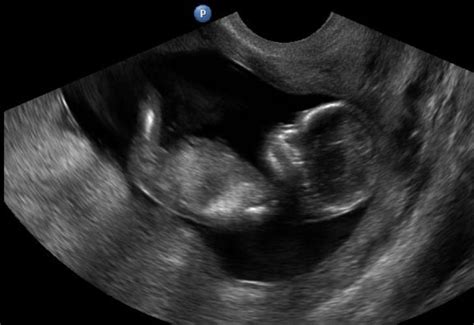

Kevés dolog éri akkora meglepetésként a leendő szülőket, mint amikor az első ultrahangvizsgálat során elhangzik az orvostól: „Itt bizony kettő van!” Az ikerterhesség híre szinte mindig sokkhatásként éri a kismamát és a párját. Leggyakrabban az első ultrahangvizsgálaton derül ki, általában a 6-9. hét között. Az ultrahangon jól látszanak a különálló embriók, valamint az is, hogy van-e közös vagy külön méhlepényük és magzatburok-rendszerük, ami segít eldönteni, hogy egypetéjű vagy kétpetéjű ikrekről van-e szó.

12 hetes 5 napos ikreink ultrahang vizsgálata :)